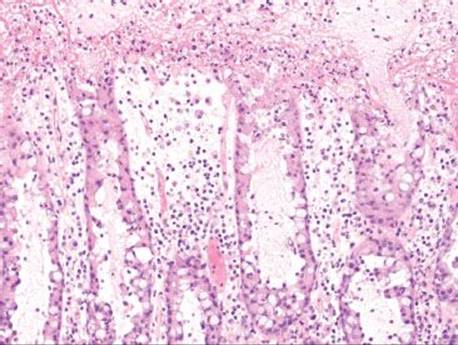

Figure 4.85 Pseudomembranous pattern. The crypt epithelium begins to slough and the lamina propria is edematous. The surface shows abundant fibrin and acute inflammatory cells.

Figure 4.86 Pseudomembranous pattern. The pseudomembrane is composed of fibrin, acute inflammatory cells, and other cellular debris.